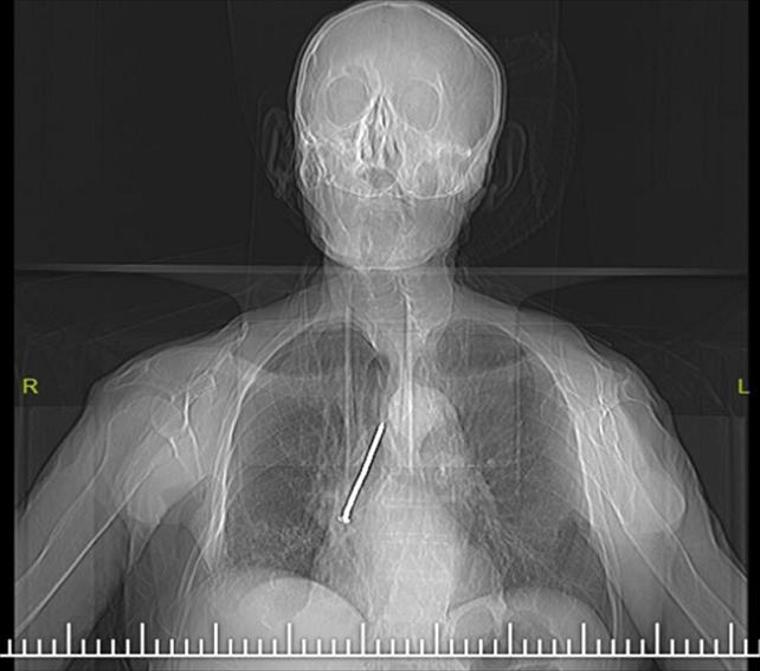

Alınan bilgiye göre, Elazığ Fethi Sekin Şehir Hastanesine öksürük ve nefes darlığı şikayetiyle başvuran 91 yaşındaki Keko Ateş'in röntgen filminde, göğsünde 10 santimetrelik çivi olduğu tespit edildi. Ateş'in soluk borusundan sağ akciğerine kaçmış olan çivi "Rijit bronkoskopi" işlemiyle çıkarıldı.

"Larenks kanseri nedeniyle 24 yıl önce larenksi (gırtlak) alınan ve boynundan nefes borusuna açılan açıklık aracılığıyla nefes alıp verebilen hastanın, nefes borusundaki bu açıklığı temizlemek amacıyla kullandığı 10 santimlik çivi, soluk borusuna kaçmış. Bunun üzerine hastamızı acil olarak ameliyata aldık. Uyguladığımız işlemi ile nefes borusundaki 10 santimetrelik çiviyi başarılı bir şekilde çıkardık. Hastamızı ameliyat sonrası bir süre serviste takip ettikten sonra sağlığına kavuşmuş bir şekilde aynı gün taburcu ettik."